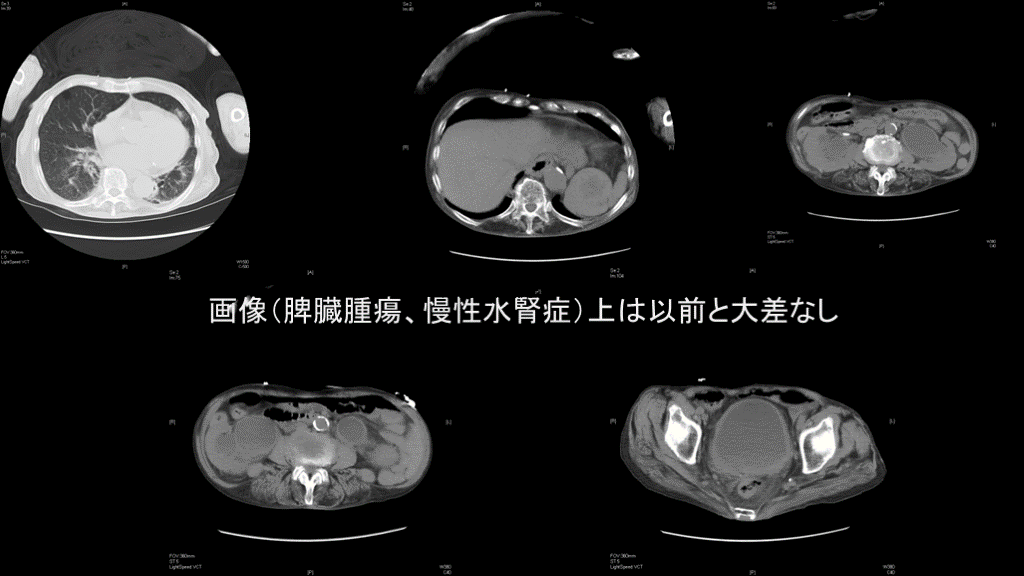

画像(脾臓腫瘍、慢性水腎症)上は以前と大差なし 神経因性膀胱・水腎症

画像検査 MRIでも著変なし. さらに